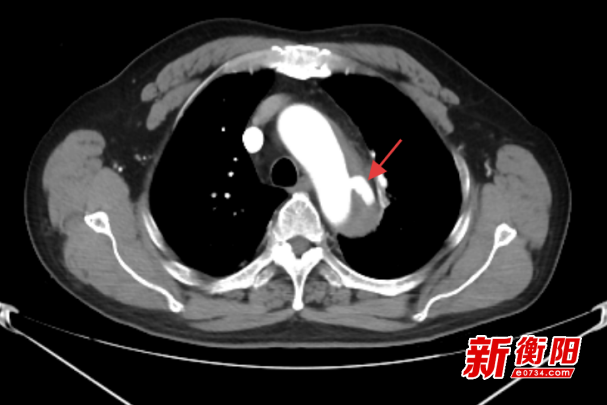

患者袁某,59岁,因“胸背部疼痛约1周”入院,主动脉CTA显示降主动脉夹层并壁内血肿形成,病情极其凶险,如不及时治疗,随时可能因血管破裂导致大出血,危及生命。考虑传统开放手术创伤大、并发症多,医师团队最终决定采用腔内介入治疗方案。

次日,手术团队在DSA(数字减影血管造影)引导下,经股动脉导入导丝导管系统,精确定位夹层破口后,释放量身定制的覆膜支架,成功隔绝血流冲击假腔。术中避开重要分支血管,全程出血不足50ml,患者术后6小时即恢复自主饮食。患者术后转入血管外科病房,48小时内即下床活动,复查显示支架位置良好,假腔内血栓形成,达到解剖学治愈。